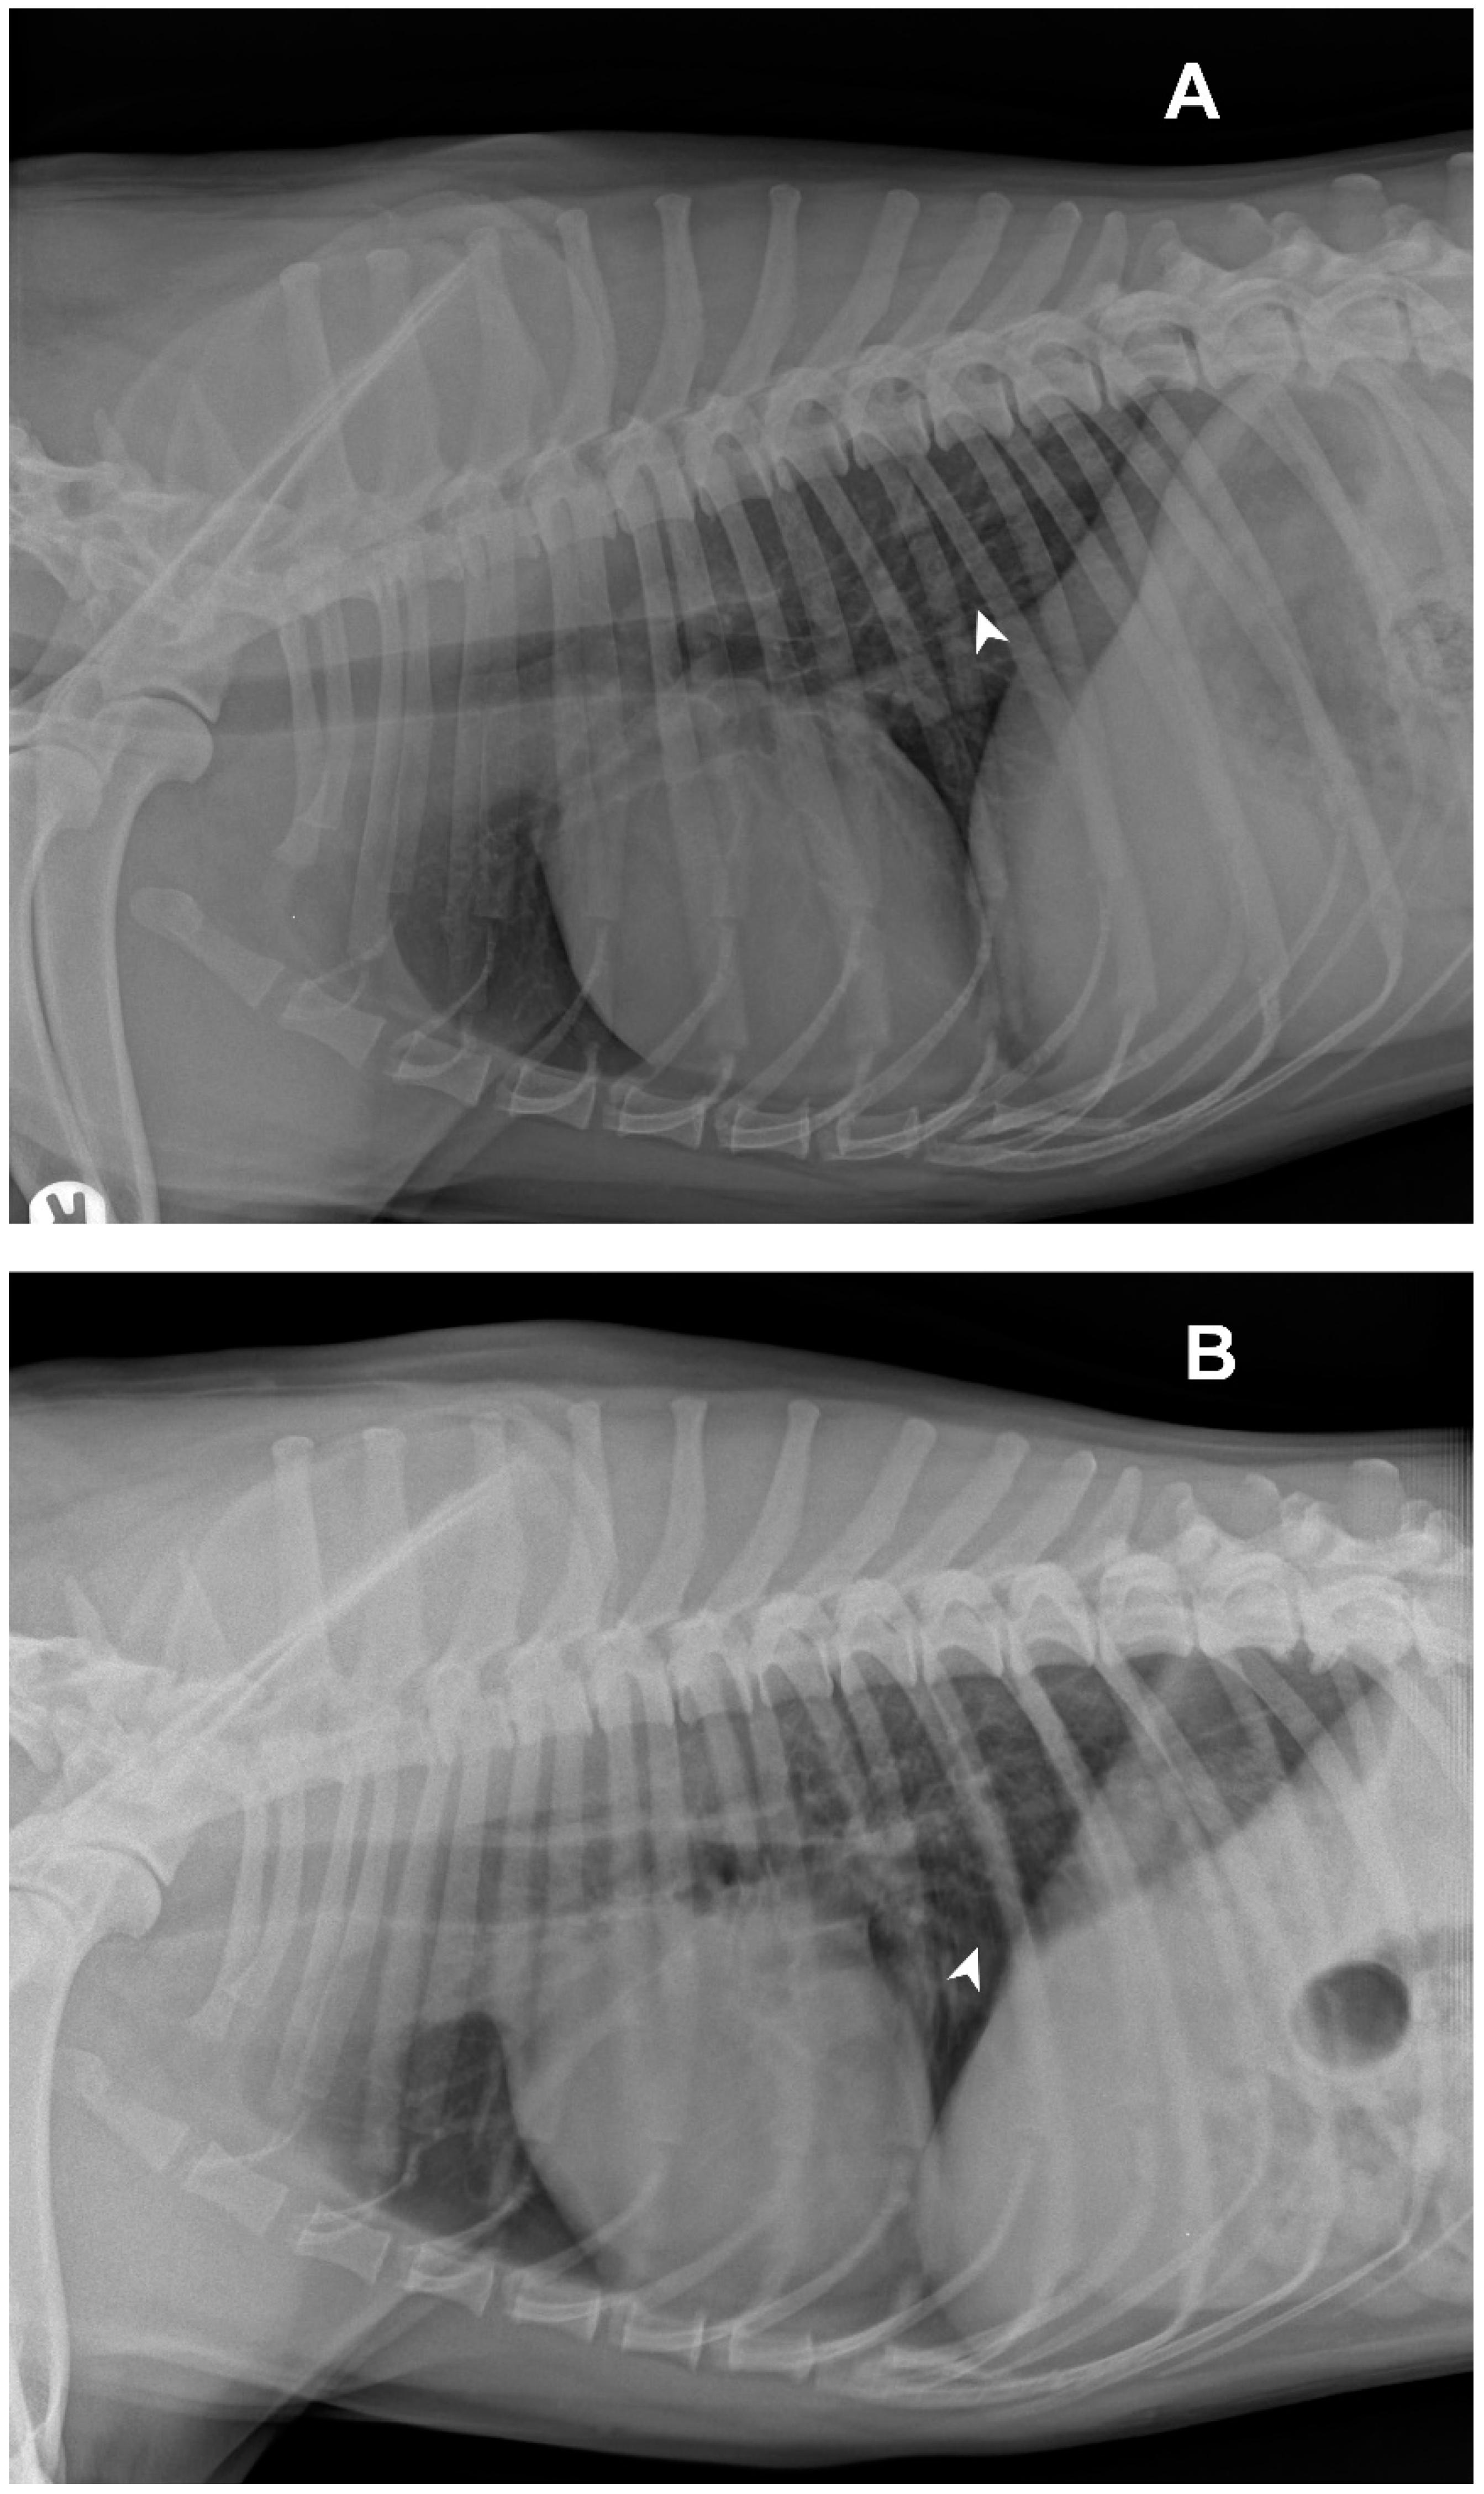

Radiological investigations of the thorax showed a diffuse unstructured interstitial pattern. The dog had a perihilar distribution and multiple lung lobes were affected (Figure 1).

Figure 1. Right (A) and left (B) latero-lateral views of the dog: white arrows indicate examples of areas with unstructured diffuse interstitial pattern.

Diagnostic imaging highlighted the elements compatible with CPIV infection, as also reported in the literature [20,26]. The cytological investigations carried out on the BALF were negative for the presence of inflammatory or infectious processes and these data should direct the diagnosis towards other etiologies. By laboratory investigations, the dog tested positive only for CPIV; this result highlights the risk to underestimate the spread of CPIV, favored by the incomplete protection provided by vaccinations [18,19,21].